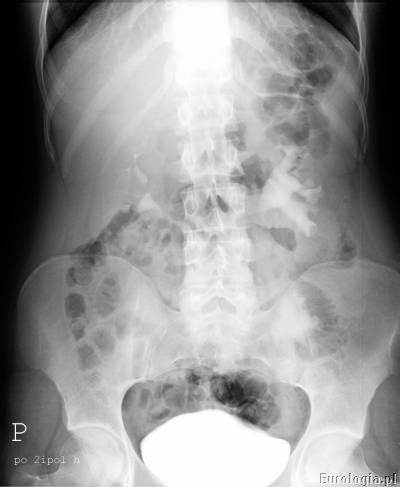

Przykładowe badanie urograficzne :

Pierwsze zdjęcie rentgenowskie po podaniu kontrastu w czasie urografii pokazuje tak zwaną fazę nefrograficzną – uwidacznia się warstwa miąższowa nerek. Już pierwsze zdjęcie wykonane podczas urografii w większości przypadków pozwala ocenić ilość nerek i ich położenie.

Kolejną fazą w badaniu jest faza wydzielnicza, w czasie której uwidocznione zostają układ kielichowo- miedniczkowy i moczowody. Urolog na podstawie zdjęć urograficznych ocenia nerki i moczowody pod kątem obecności w nich złogów, wad anatomicznych – np. zwężenie połączenia miedniczkowo – moczowodowego lub nowotworów. Nowotwory urothelialne występujące w układzie kielichowo – miedniczkowym lub moczowodzie widoczne są jako ubytki wypełnienia. W przeszłości urografia była podstawową metodą rozpoznawania guzów nerki.

Mocz spływający z układu kielichowo – miedniczkowego moczowodami do pęcherza zakontrastowuje układ moczowy dzięki czemu na zdjęciach rentgenowskich możliwa jest ocena czy spływ jest swobodny, czy utrudniony. W przypadku utrudnionego spływu badanie z reguły pozwala na ocenę miejsca i rodzaju przeszkody.

Zakontrastowany mocz spływając do pęcherza wypełnia go co umożliwia ocenę jego wnętrza. Guzy pęcherza mogą być widoczne jako ubytki wypełnienia. W czasach kiedy nie było dostępu do ultrasonografii zdjęcie urograficzne wykonane po oddaniu moczu było podstawą do oceny stopnia zalegania moczu po mikcji.